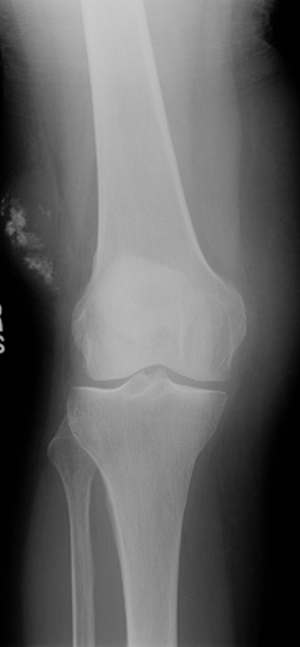

Plain radiographs of the affected area

are important for the evaluation of soft tissue mineralization and bony

involvement. In addition, any patient with a mass suspicious for soft

tissue sarcoma should have a chest x-ray. -

Any soft tissue sarcoma can present with soft tissue calcifications.

-

The most common masses with soft tissue mineralization:

Myositis ossificans (more mature mineralization around periphery)

Hemangioma (small, round, well-defined phleboliths; Fig. 2-1)

Synovial sarcoma (variable pattern of mineralization)

Well-differentiated liposarcoma

Extraskeletal chondrosarcoma

Extraskeletal osteogenic sarcoma (centrally mature mineralization; Fig. 2-2)

Figure 2-1 Soft tissue phleboliths. Diagnosis: Hemangioma.

Figure 2-2 Soft tissue mineralization. Diagnosis: Extraskeletal osteogenic sarcoma.P.32